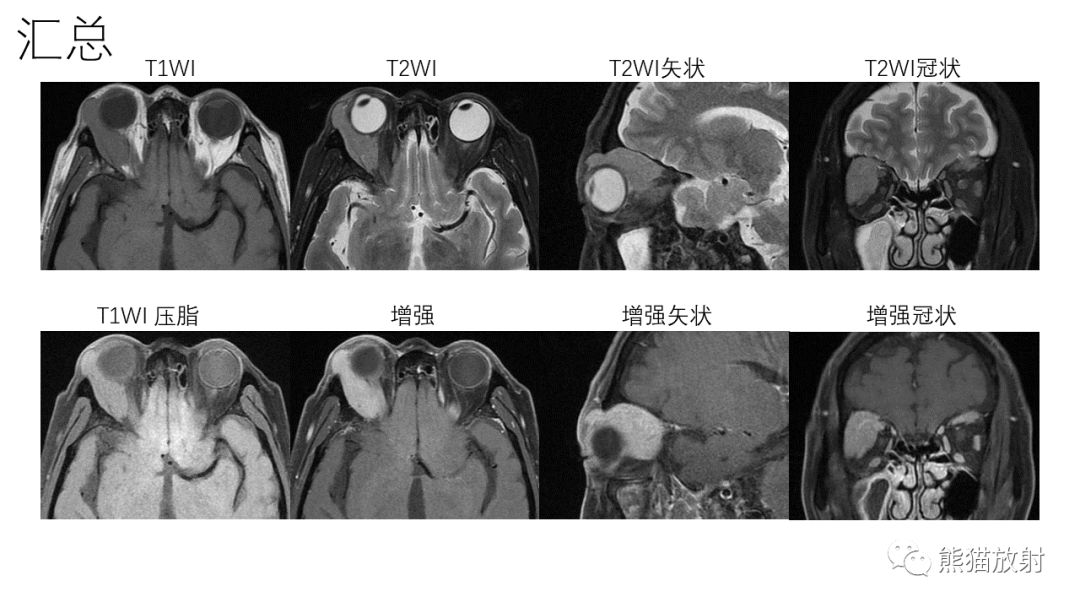

【PPT】泪腺多形性腺瘤 VS 眼眶淋巴瘤-1